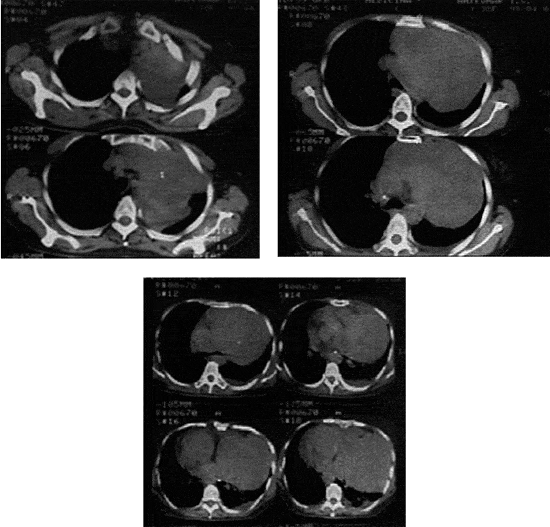

КТ органов грудной полости при опухолях средостения!